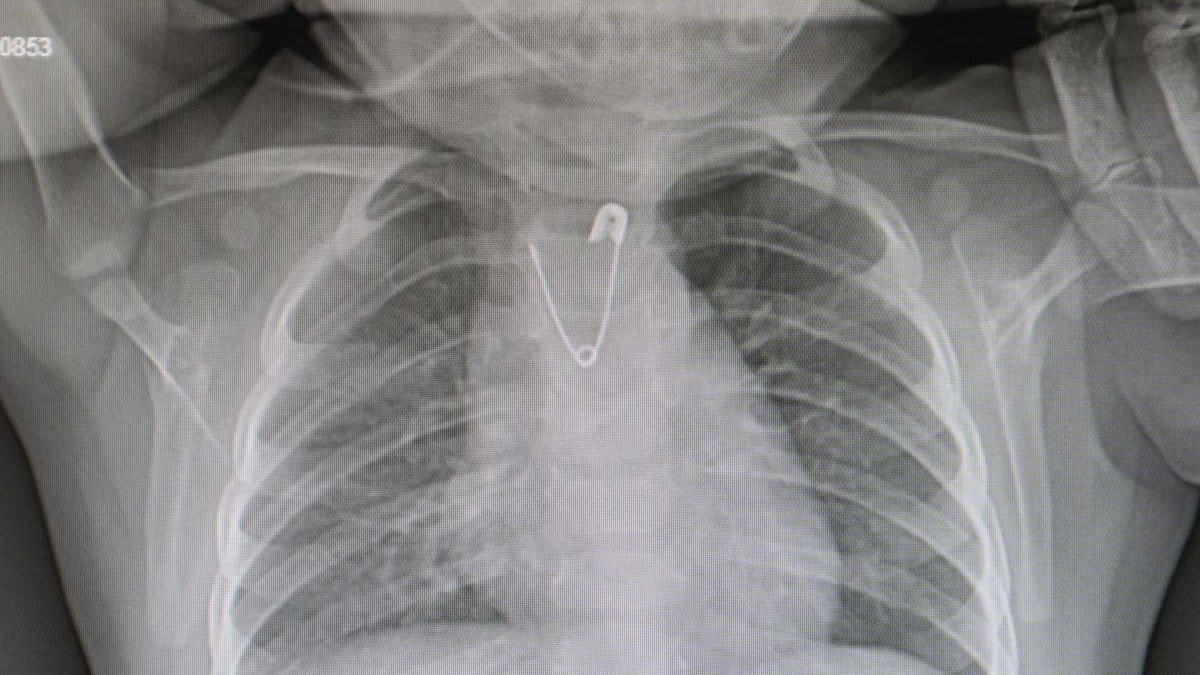

Çocuk Cerrahisi Uzmanı Doç. Dr. Doğuş Çalışkan, "Bebeğimizin acil serviste çekilen akciğer grafisinde açık ağızlı bir çengelli iğnenin yemek borusunun en dar yeri olan üst kısmı tıkadığını gördük. Bu da çocuğumuzun kusmasına, beslenememesine neden oluyordu. Hemen ameliyathaneye alarak anestezi altında yapılan endoskopi işlemiyle çengelli iğneyi çıkarttık." bilgisini paylaştı.

Operasyonun anlatıldığı kadar basit bir işlem olmadığını, bebeğin yuttuğu çengelli iğnenin ucunun açık olmasının cerrahi olarak çıkarılmasını da zorlaştırdığını vurgulayan Çalışkan, "Bu işlem yapılırken yemek borusunda yırtık, kanama ve ciddi hayati tehlike yaratan durumlar söz konusu olabilirdi. Ama işlemi başarıyla gerçekleştirdik, şu anda her şey yolunda, bebeğimiz beslenebiliyor." diye konuştu.